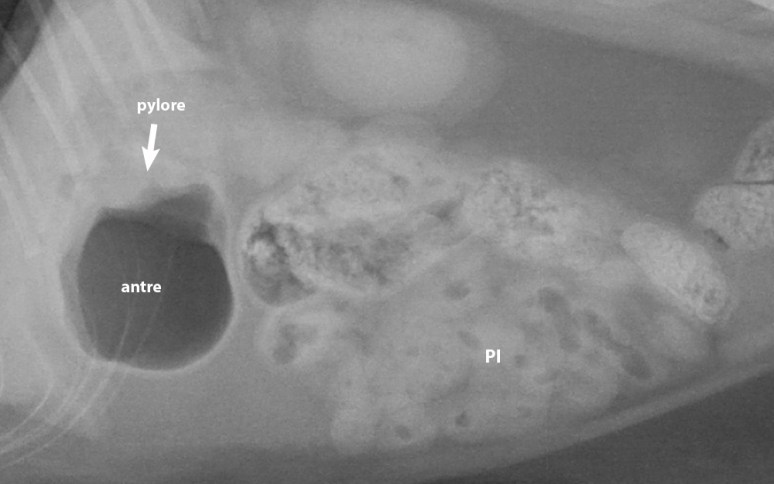

La majorité d’entres vous suspectiez une obstruction intestinale par un corps étranger linéaire (à 61%) ou une obstruction pylorique (22%). Ça faisait du sens compte tenu de certains des signes observés… Les obstructions linéaires montrent de façon typique de petites bulles de gaz au contour irrégulier – parfois en forme de goutte d’eau ou de virgule – en raison des nombreux replis intestinals. Le gaz intestinal se voit ainsi séquestré et « moulé » par les parois internes repliées – comme un accordéon – au lieu de se conformer à des parois arrondies, formant normalement des bulles rondes ou ovales. Certaines des bulles étaient un peu irrégulières chez ce chat, mais la majorité montraient un contour relativement arrondi. Le diamètre intestinal restait normal – i.e. moins de 13 mm de séreuse à séreuse, ou moins de 2 fois la hauteur de la plaque terminale crâniale de L2 (référence: Adams et al. 2012) – ce qui est toutefois normal dans un cas d’obstruction linéaire qui ne cause généralement pas d’obstruction luminale complète. Le petit intestin (PI) se trouve regroupé dans l’abdomen moyen droit, ce qui est aussi souvent observé chez des chats normaux. Comme l’apparence du PI nous inquiétait aussi – du moins suffisamment -, nous avons effectué une échographie, laquelle n’a toutefois pas révélé de corps étranger, mais des signes d’entérite (liquide intestinal avec parois un peu épaissies). La paroi gastrique était aussi un peu irrégulière.